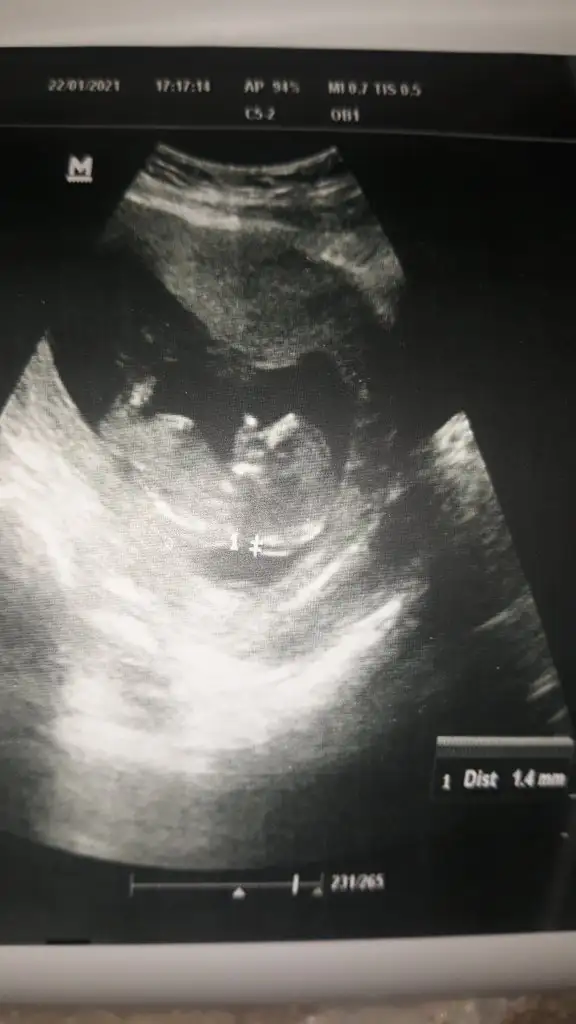

• 20210122_212620.webp

20210122_212620.webp

18,5 KB · Görüntüleme: 76

• 20210122_212608.webp

20210122_212608.webp

22,4 KB · Görüntüleme: 59

• 20210122_212559.webp

20210122_212559.webp

26 KB · Görüntüleme: 73